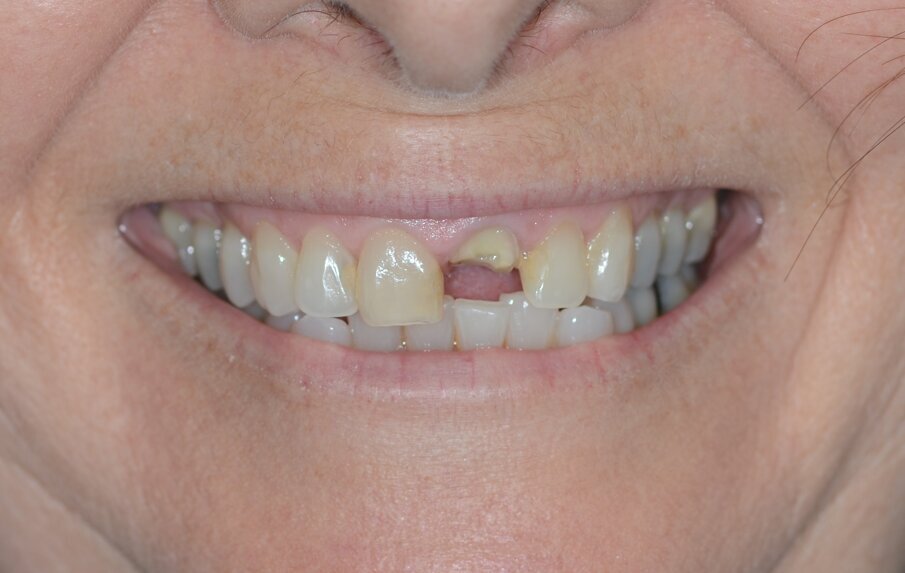

Una paziente di 53 anni si è presentata in studio con un incisivo sinistro fratturato a cui era stata più volte cementata una corona di ceramica (Figg. 1, 2). L’anamnesi e gli esami hanno evidenziato una buona salute sistemica e orale, un’occlusione ben equilibrata e nessuna abitudine al fumo. La tomografia cone beam (CBCT) e la radiografia periapicale hanno mostrato un riassorbimento radicolare esterno con inserimento nell’osso alveolare molto scarso, insufficiente per un adeguato posizionamento di un comune perno endocanalare (Figg. 3, 4). Considerando che il dente fratturato si trovava nella zona estetica, il paziente richiese un restauro nel modo più sicuro e più veloce possibile.

Fig. 1_Situazione iniziale, visione extra-orale.

Fig. 2_Situazione iniziale, visione intra-orale.